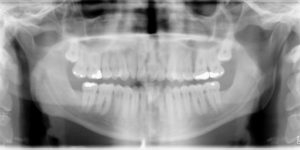

A 34.7 year old Caucasian male presents with a chief complaint that “I want to fix my bite”